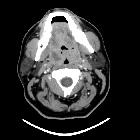

CT

- rim-enhancing fluid collection adjacent to an enlarged and inflamed tonsil

- 75% specific and 100% sensitive at diagnosing peritonsillar abscess

- false positives are due to the similar appearances of peritonsillar abscess and phlegmon